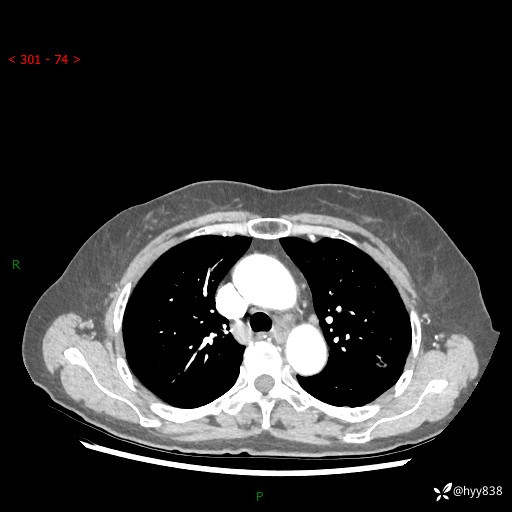

胸部CT(2024.7.16)